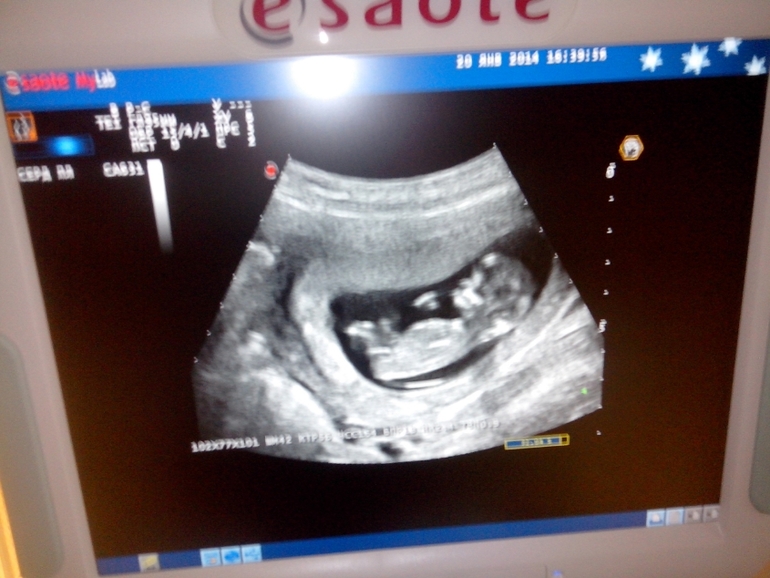

Наш 1-ый скрининг! Моя любимая детка, моя радость, моя жизнь!!!!!

Какое прекрасное чудо =))) Фотография просто супер!!

одна из моих любимых сейчас))) фотографий.Спасибо!

Только сейчас увидела подпись после 2й фотки) У нас тоже очень активный малыш, прям как будто знал, что на него смотрят, показал себя во всей красе =) Узист сказал, что пол сейчас непонятен, но нам с мужем показалось, что мальчик!

Ну вот и сходили мы на УЗИ) на подходе экватор)